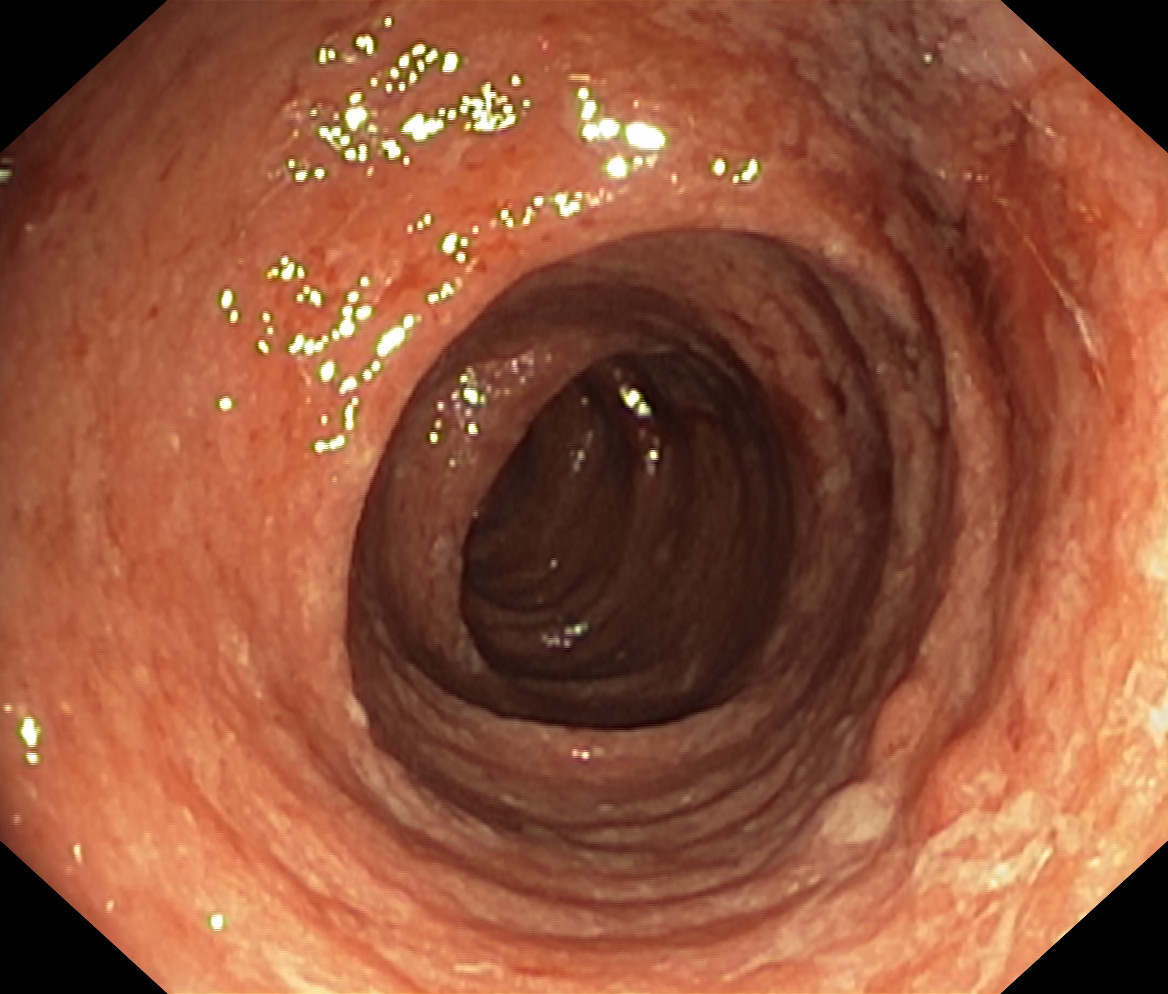

Zapalenie wrzodziejące jelita grubego